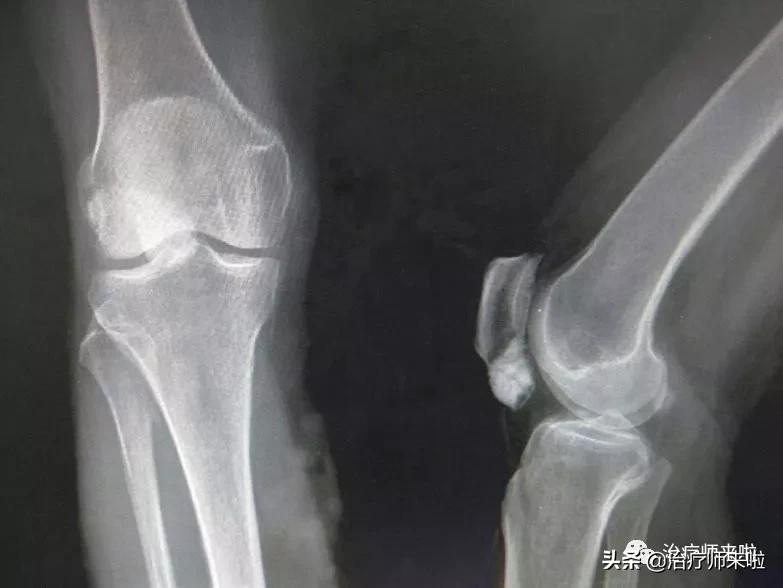

(二)影像学检查

影像学检查包括X线、CT和磁共振等,对髌骨脱位的诊断有很大的价值,X线可以显示髌骨的形态和位置,CT相对于X线更加灵敏,磁共振有助于评估软骨和软组织的损伤。